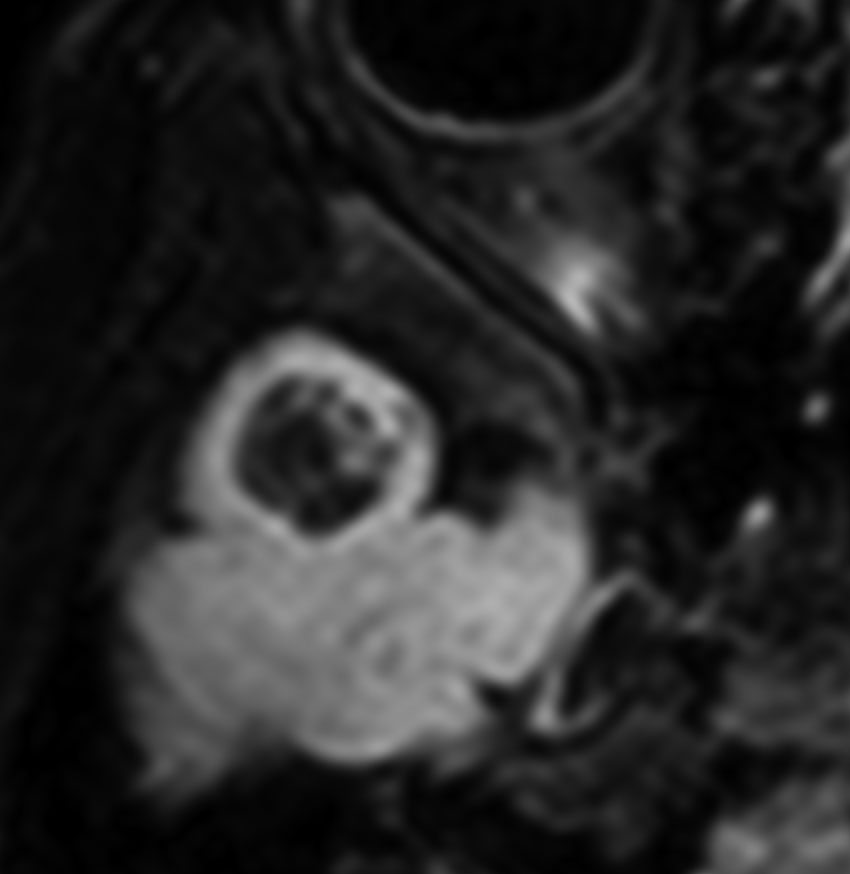

乳児期にてんかん発作で発症する内側側頭葉過誤腫

mesial temporal hamartomatous tumor

乳児期に全身性感帯痙攣発作で発症しました。左海馬鈎に強い石灰化があります。側頭葉硬化症とも言われるものです。この部位の過誤腫様の腫瘍は難治性てんかんとなることが多く,病変切除が必要となります。

脳波では前頭葉に蕀律動を認めます。切除は扁桃体と海馬鈎の摘出を目指すものです。